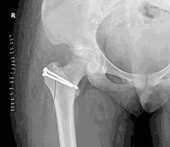

髋关节脱位合并股骨头骨折是髋关节常见创伤之一,既往采用牵引复位、后侧入路的切开复位均有较高的股骨头坏死率。急诊条件下,经SHD行股骨头骨折切开复位、清理髋关节内碎屑、处理髋臼后壁、复位固定股骨头骨折片,股骨头血运得到最大限度地保护,创伤性关节炎和股骨头坏死率降至最低水平。见图3。